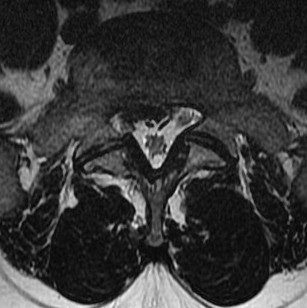

MRI

T2 Sagittal - myelogram

T1 Axial - see nerve root against white fat

MRI changes

1. Central root clumping

2. Empty sac appearance

3. Soft tissue mass in subarachnoid space